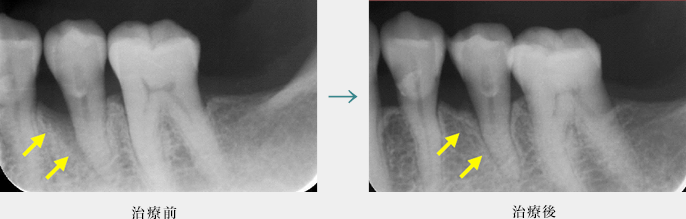

再生療法

歯周病の進行によって溶けてしまった骨を、歯周再生療法によって回復しています。

歯周病による骨の溶け具合は、歯の形態や位置によって様々です。

歯の裏側だけに限局していることもあれば、歯の全周で進行することもあります。